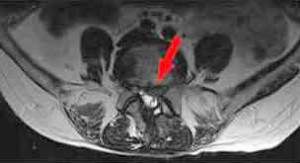

bandscheibe3